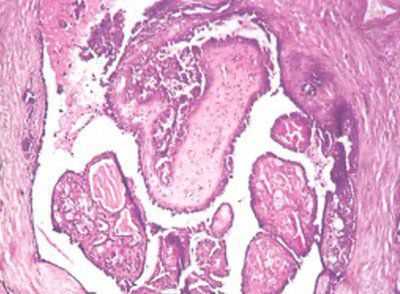

Внутрипротоковая папиллома — округлое образование с четкой границей размером 3-4 см, но возможны процессы, занимающие несколько сантиметров в диаметре. Внутрипротоковая папиллома представлена сосочковыми разрастаниями, состоящими из фиброваскулярной ножки, покрытой эпителием и миоэпителием (фото 20). Часто отмечают апокринизацию эпителия.

Фото 20. Внутрипротоковая папиллома. Гематоксилин-эозин, х 200

Фото 21. Внутрипротоковая папиллома. Видны отдельные сосочки с фиброзной стромой и однорядной эпителиальной выстилкой. Гематоксилин-эозин, х 200